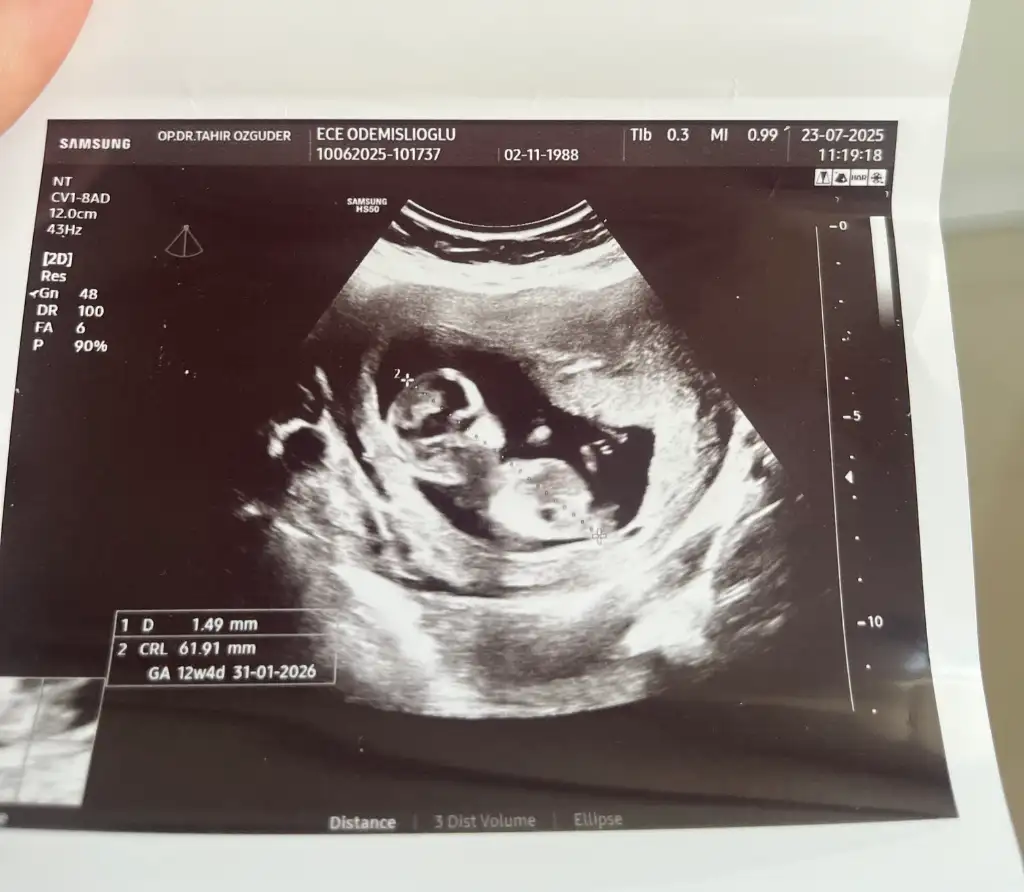

Benziyor canım gerçekten ama erkek olsa 13. haftada söylemez miydi doktor? Erkekler erken gösteriyor sanki kendini.

Sağlıkla gelsinler de önemli değil belli olur bir iki haftaya erken henüzBenziyor canım gerçekten ama erkek olsa 13. haftada söylemez miydi doktor? Erkekler erken gösteriyor sanki kendini.